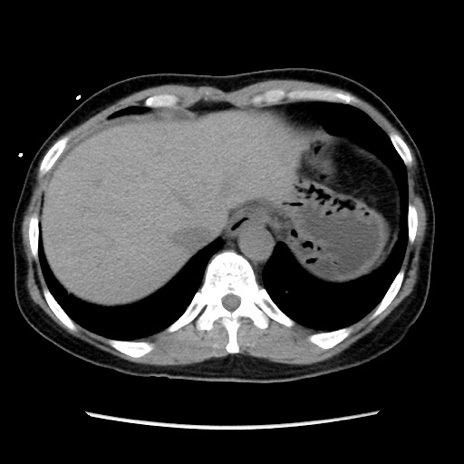

症例10(横断像)

【症例】 50歳代女性

【主訴】 腹痛

【現病歴】前日生レバーを食べた。今朝に排便あり。 昼前に突然発症の腹痛を生じ、当院救急外来を受診した。

【身体所見】 意識清明、腹部:平坦、軟、下腹部やや左を中心に圧痛・反跳痛あり、筋性防御あり

【データ】WBC 7800、CRP 0.07